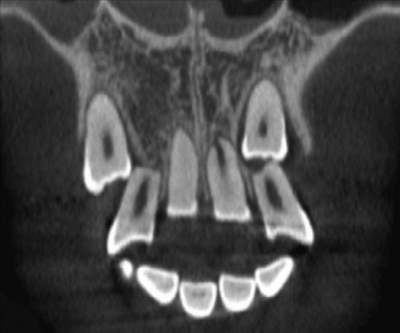

11 歳の女児。上顎両側犬歯部の空隙を主訴として来院した。前歯部の被蓋関係は正常である。初診時の口腔内写真、エックス線画像及び歯科用コーンビーム CTを別に示す。まず行うべき対応はどれか。1つ選べ。

a. 経過観察

b. 上顎中切歯間の空隙閉鎖

c. 上顎両側犬歯の開窓牽引

d. 上顎両側側切歯の歯内療法

e. 上顎両側第一小臼歯の近心移動